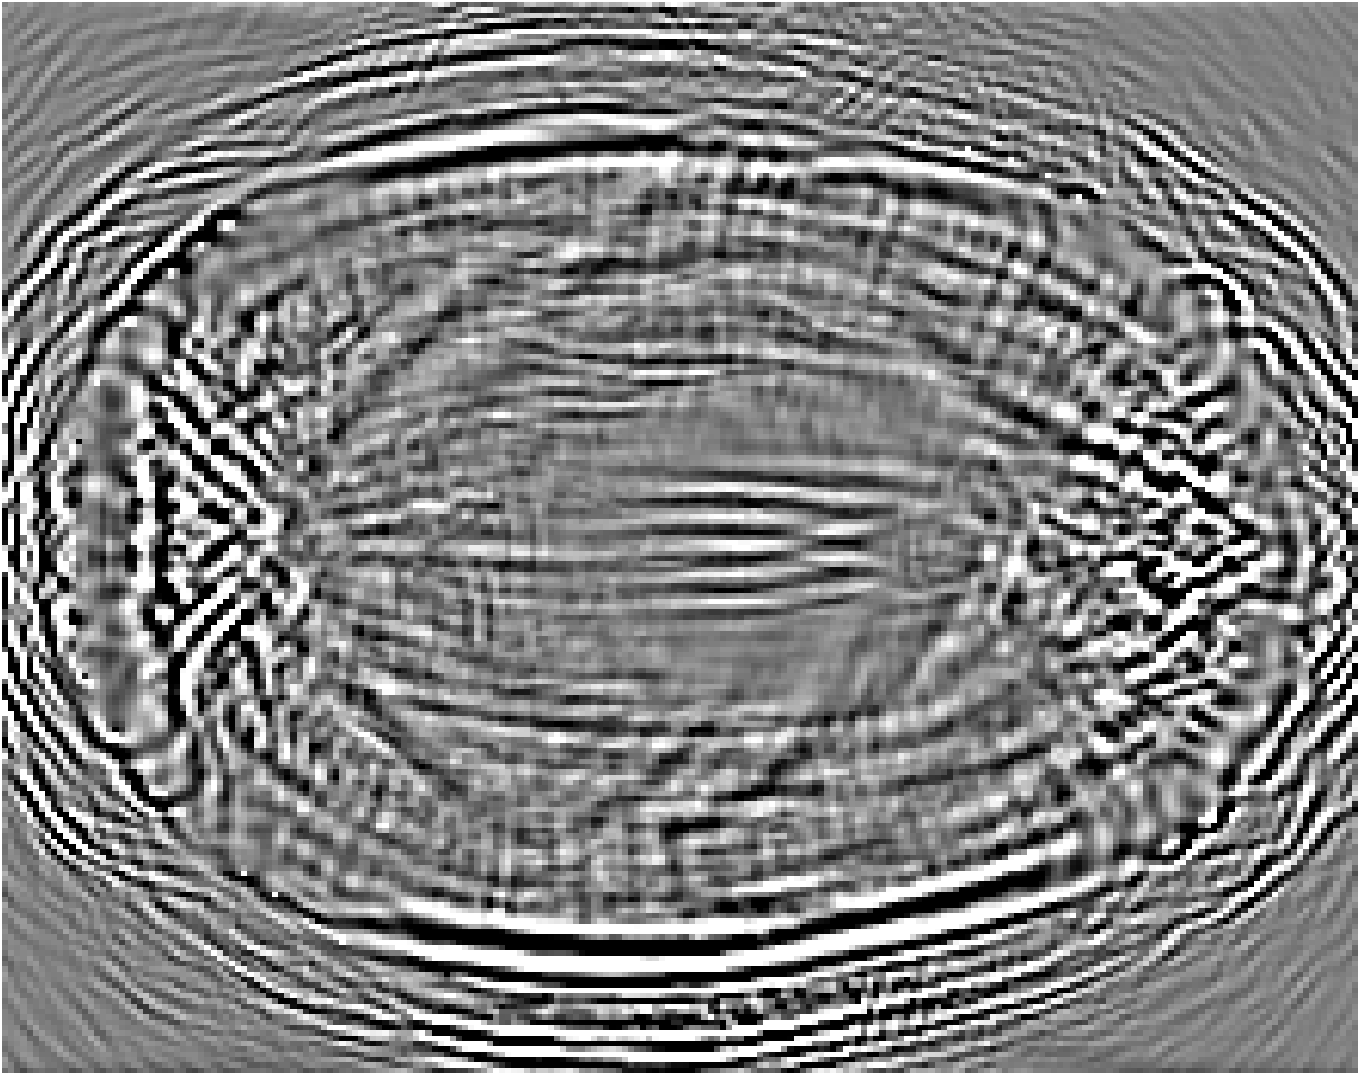

Figure 7: Stacked TRA Image with (a) Partial-transducer dataset and (b) Full-transducer dataset

To evaluate performance, we construct two acquisition setups using the same horizontal 2D slice of the phantom: (i) an idealized full-transducer dataset (Figure 3(b)) providing near-uniform coverage along the head contour, and (ii) a partial-transducer dataset (Figure 6) designed to reflect practical acquisition constraints. In the partial setup, a linear array with 51-element is repositioned around the head; for each view, the central element transmits and all other 50 elements receive. The partial setup includes 50 sweeps covering the full 360, meaning that for each sweep, the source and receivers rotate by 360/50=7.2360/50=7.2^{\circ}. Sweeping 50 views yields, per 2D slice, a channel tensor of shape (T,Ns,Nr)=(5001,50,50)(T,N_{s},N_{r})=(5001,50,50). The key distinction between these two datasets is their aperture: full-transducer provides near 360 coverage in a single placement, whereas partial-transducer attains coverage by aggregating neastest 50 receivers in a single placement, which is only around 36. Particularly, the partial-transducer setup includes only 50 sweeps, while the full-transducer setup uses all receivers covering the entire brain, with each transducer acting as a source in turn while the others serve as receivers. Compared to the full-transducer, the partial-transducer achieves coverage by combining a much smaller number of views. For each sweep, we generate the forward wavefield g(𝐱,t|𝐠){{g}}(\mathbf{x},t|\mathbf{g}) and the back-propagated wavefield p~(𝐱,t|𝐠)\tilde{{p}}(\mathbf{x},t|\mathbf{g}) and generate the TRA fragment with Eq. (7) (example in Figure 6). With the physical TRA method, the TRA fragment can be stacked to give the stacked TRA image. To validate the differences between the two datasets, we generated stacked TRA images using both datasets, as shown in Figure 7. As shown in Figure 7(b), the full-transducer dataset provides significantly greater detail in internal structures. Despite higher levels of noise and artifacts caused by the limited number of views, the partial-transducer dataset is still capable of capturing some meaningful tissue structures.